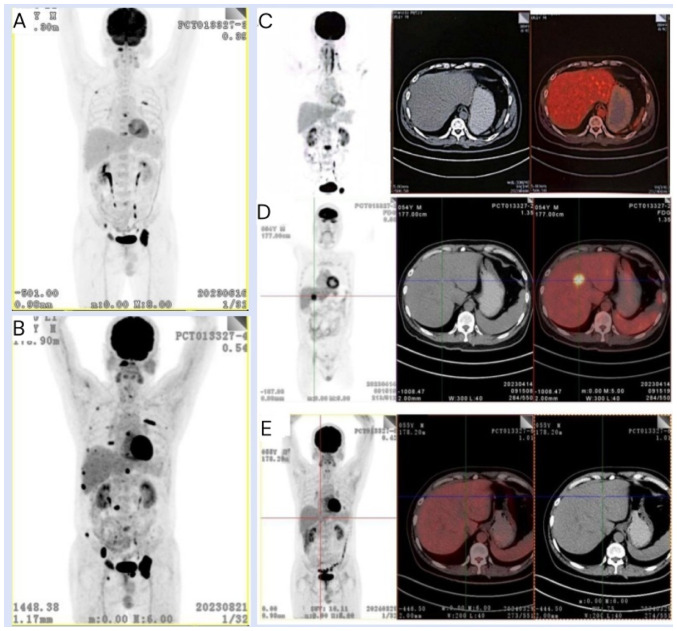

多发性骨髓瘤(MM)是一种以骨髓浸润和血液和尿液中存在单克隆蛋白为特征的克隆性浆细胞恶性肿瘤。然而,尽管在治疗方面取得了进展,但复发/难治性MM (RRMM)仍然是一个重大挑战。嵌合抗原受体(CAR)-T细胞疗法是一种很有前途的治疗RRMM的方法,它涉及到t细胞的工程化,以表达靶向肿瘤细胞上特定抗原的CAR。本病例报告提出了一例伴有肝髓外疾病(EMD)的RRMM患者,在CAR-T细胞治疗后达到严格的完全缓解。本病例报告强调了CAR-T细胞治疗RRMM的疗效,并讨论了患者的临床病程、治疗结果和副作用,此外,还回顾了有关CAR-T细胞治疗EMD的文献。

Multiple myeloma (MM) is a clonal plasma cell malignancy characterized by bone marrow infiltration and the presence of monoclonal proteins in the blood and urine. However, despite the advances that have been made in terms of its treatment, relapsed/refractory MM (RRMM) remains a significant challenge. Chimeric antigen receptor (CAR)-T cell therapy, which involves the engineering of T-cells to express CARs targeting specific antigens on tumor cells, has emerged as a promising therapeutic approach for RRMM. The present case report presents a patient with RRMM with liver extramedullary disease (EMD) who achieved stringent complete remission following CAR-T cell therapy. This case report highlights the efficacy of CAR-T cell therapy in treating RRMM, also discussing the patient's clinical course, treatment outcomes and side effects, and moreover, a review of the literature that focuses on the treatment of EMD using CAR-T cell therapy.